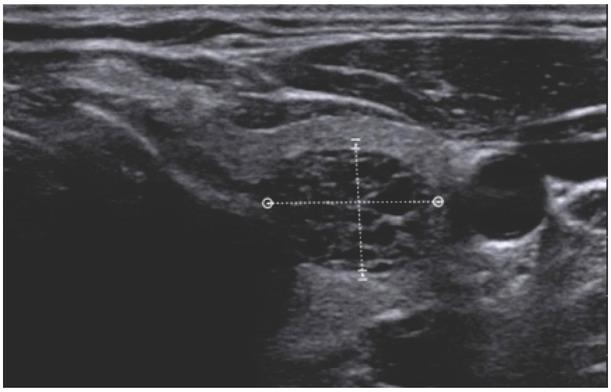

Fig. 2